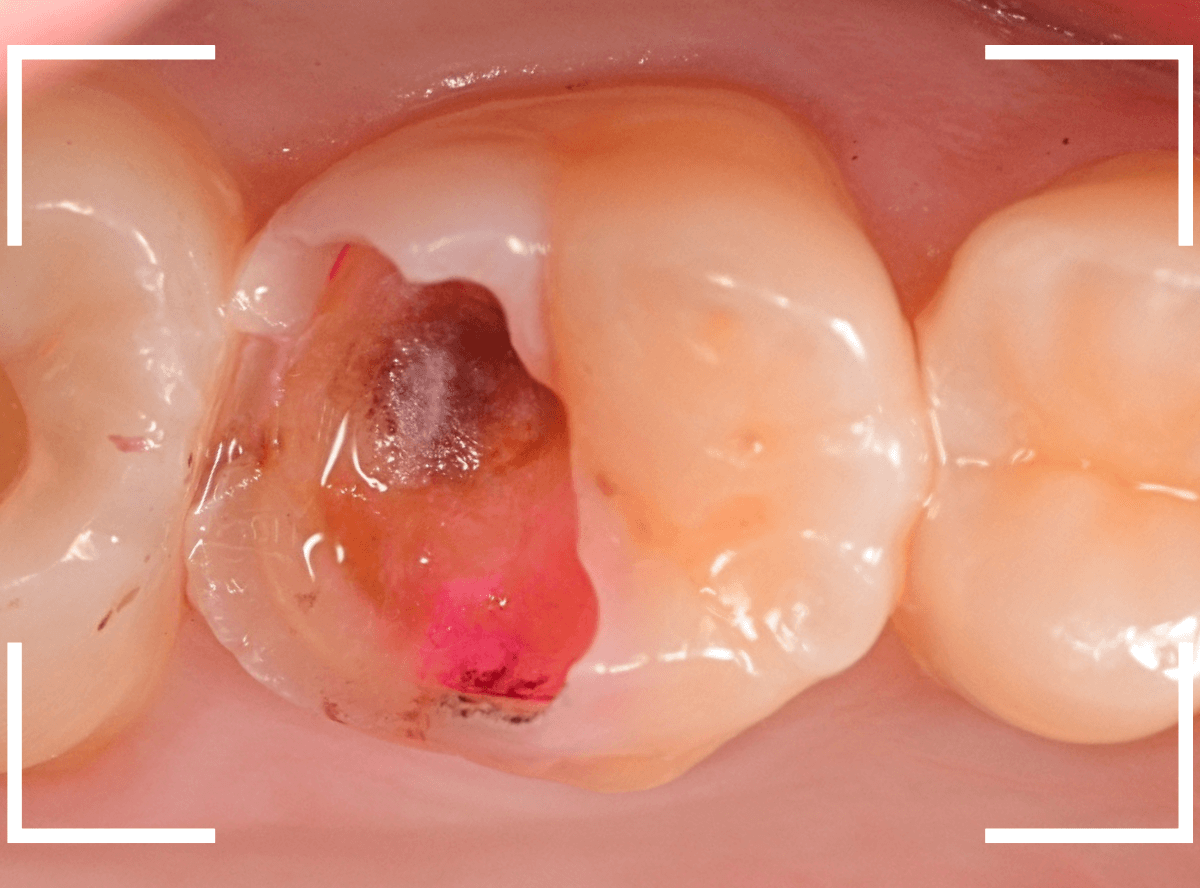

Case.14 CR(コンポジット・レジン)の下の深い虫歯

奥歯で咬んだ時に、痛みを感じるという訴えで来院された患者さんです。

パッと見は特に問題なさそうな状態ですが、大きなレジン治療がしてあり、レジンの奥もボヤっと黒っぽく見えてアヤシイ感じです。

麻酔をして、治療を開始します。

レジンを外すと、中から出血してきました。

これは、歯のスキマに歯肉が入り込んでしまったために起こってしまったものです。

おそらく、随分前から虫歯が進行していたと思われます。

止血しながら、電気メスで歯の中に入り込んだ歯肉を除去します。

虫歯と入り込んだ歯肉でぐちゃぐちゃになっている状態でした。

これでは、痛みが出てもおかしくありません。

慎重に全ての虫歯を除去したところです。

〇部が神経の入り口が見えているところです。

神経を保護する処置をして、しばらく経過観察しますが、痛みが出て神経を除去する必要が出る可能性も高いです。

痛みが出ませんように・・・。